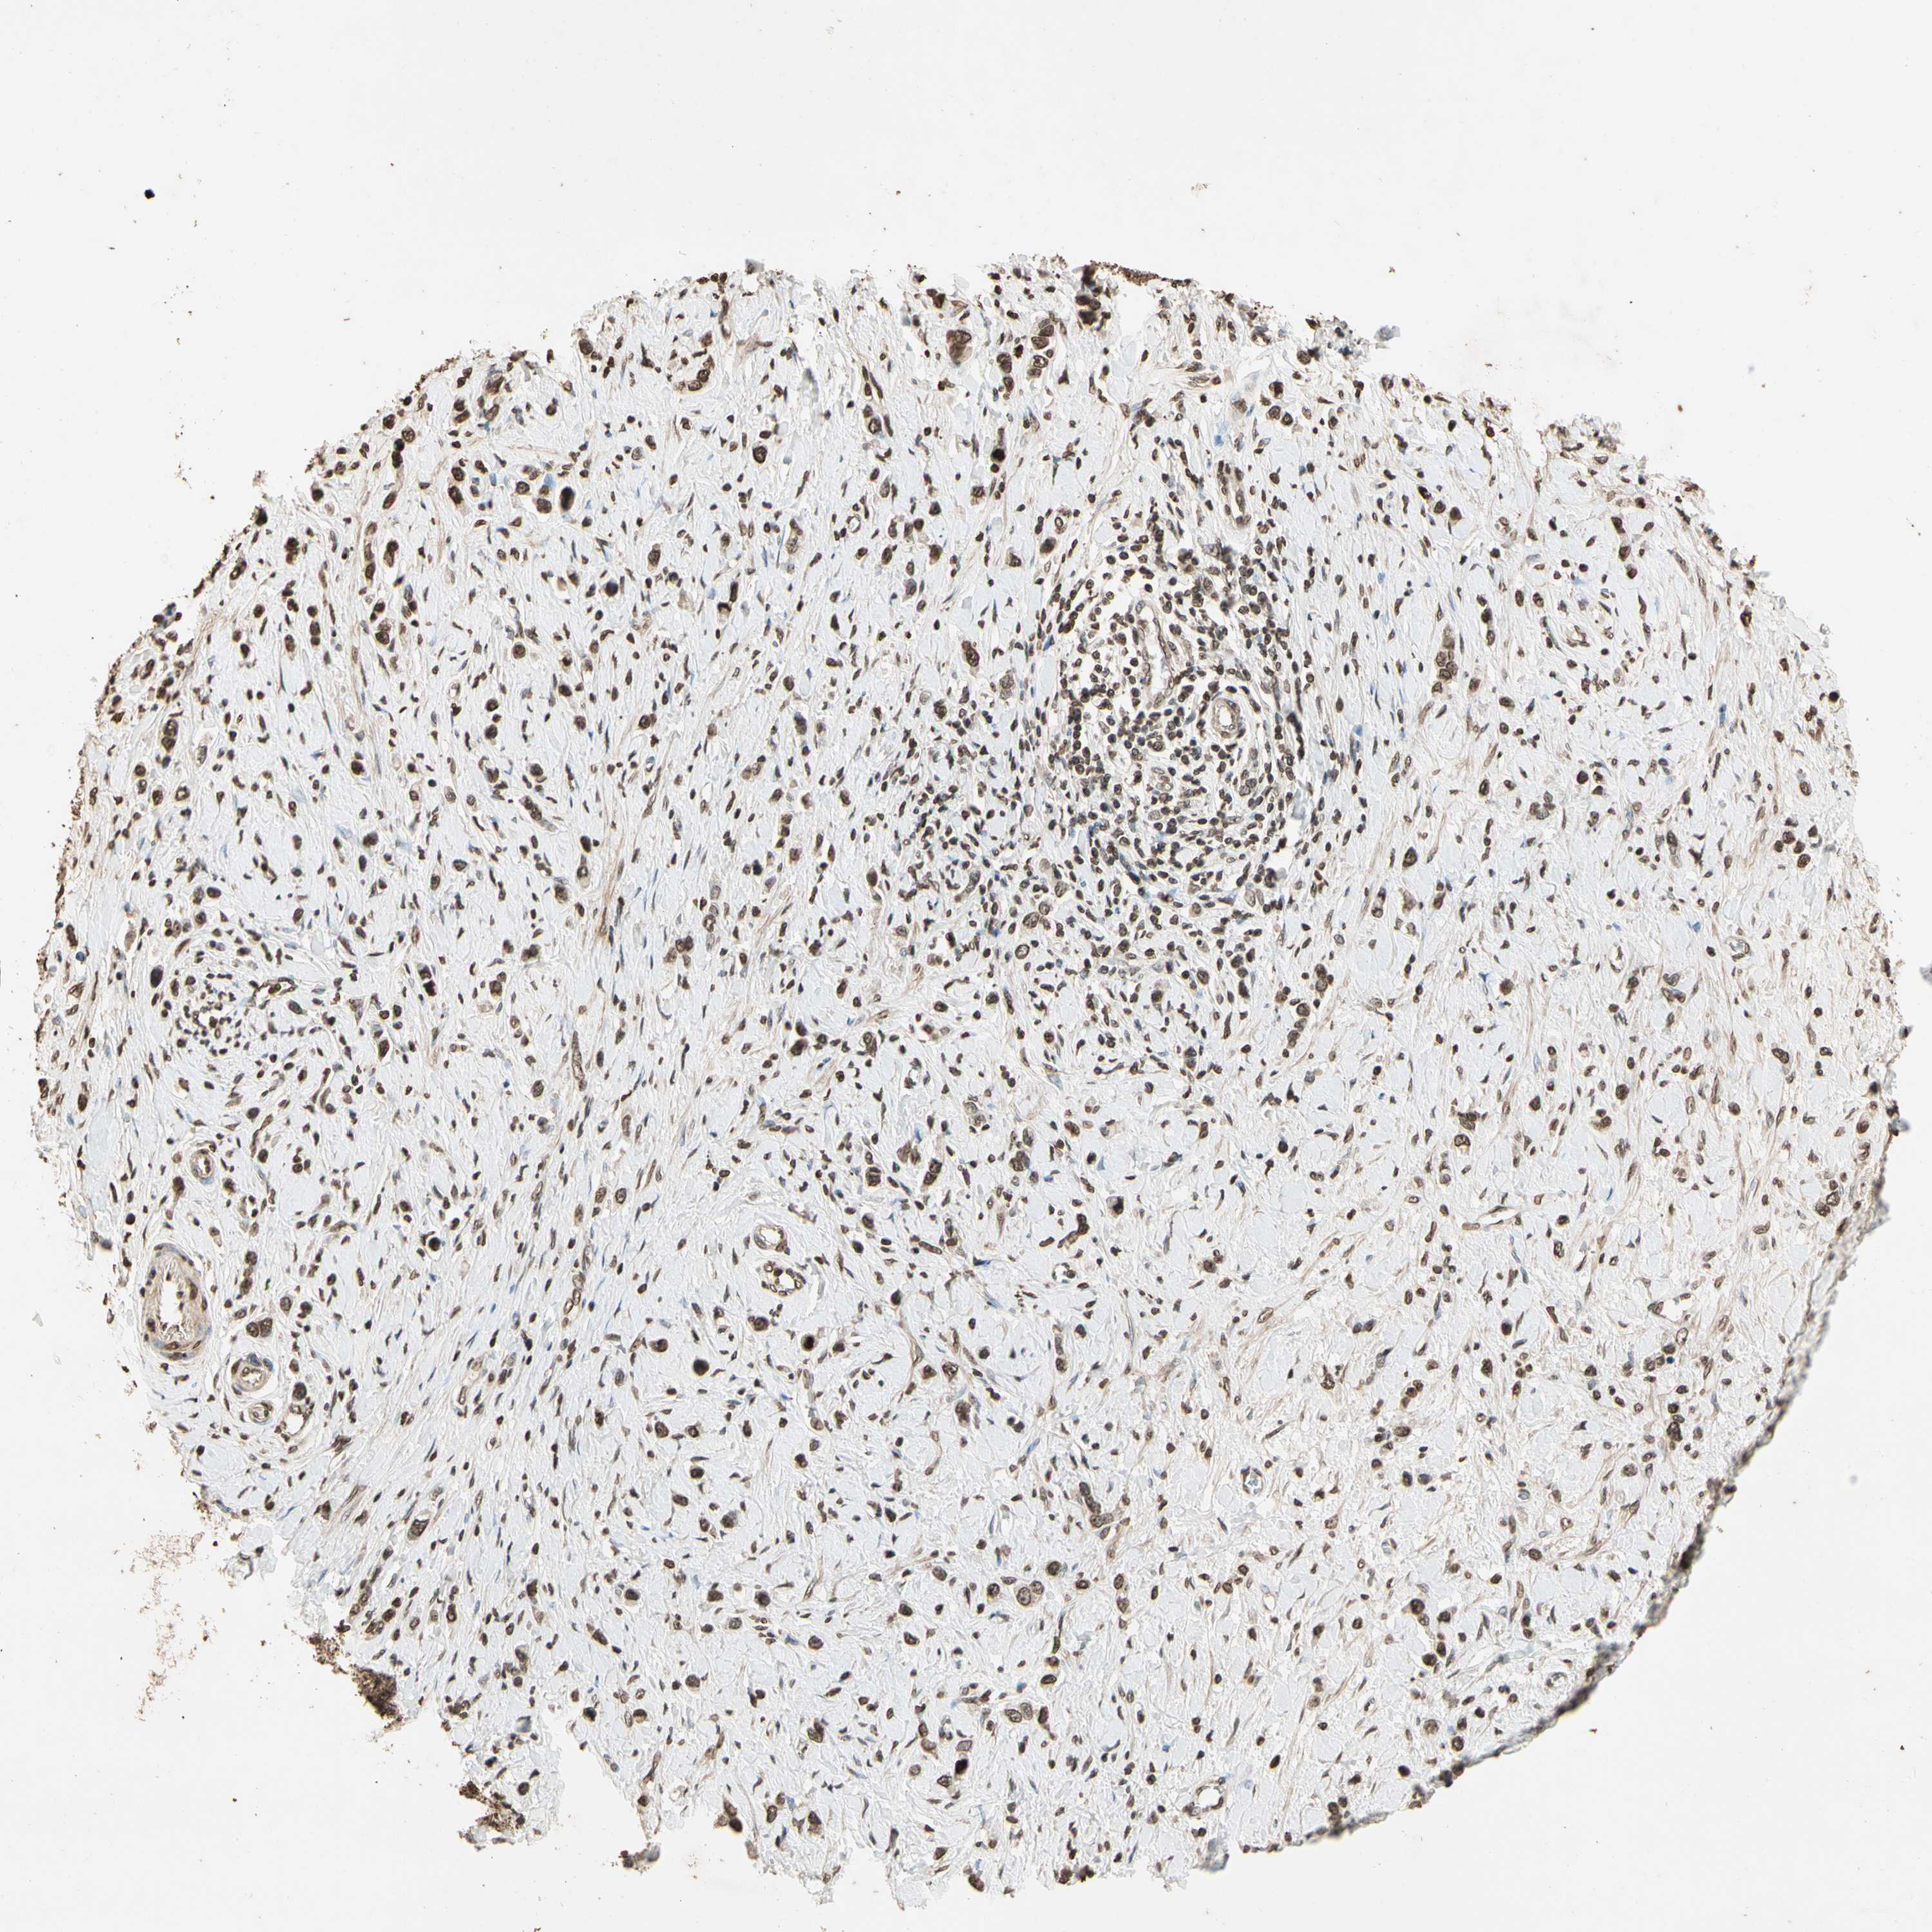

STOMACH CANCER - Protein expressioni

A mouse-over function shows sample information and annotation data. Click on an image to view it in a full screen mode. Samples can be filtered based on level of antibody staining by selecting one or several of the following categories: high, medium, low and not detected. The assay and annotation is described here.

Antibody stainingi

Antibody staining in the annotated cell types in the current human tissue is reported as not detected, low, medium, or high, based on conventional immunohistochemistry profiling in selected tissues. This score is based on the combination of the staining intensity and fraction of stained cells.

Each image is clickable and will lead to virtual microscopy that enables deeper exploration of all samples and also displays staining intensity scores, fraction scores and subcellular localization as well as patient and tissue information for each sample.

Antibody HPA019039

Antibody CAB009058

Staining

High

Medium

Low

Not detected

Intensity

Strong

Moderate

Weak

Negative

Quantity

>75%

75%-25%

<25%

None

Location

Nuclear

Cytoplasmic/membranous

Cytoplasmic/membranous,nuclear

Adenocarcinoma, NOS